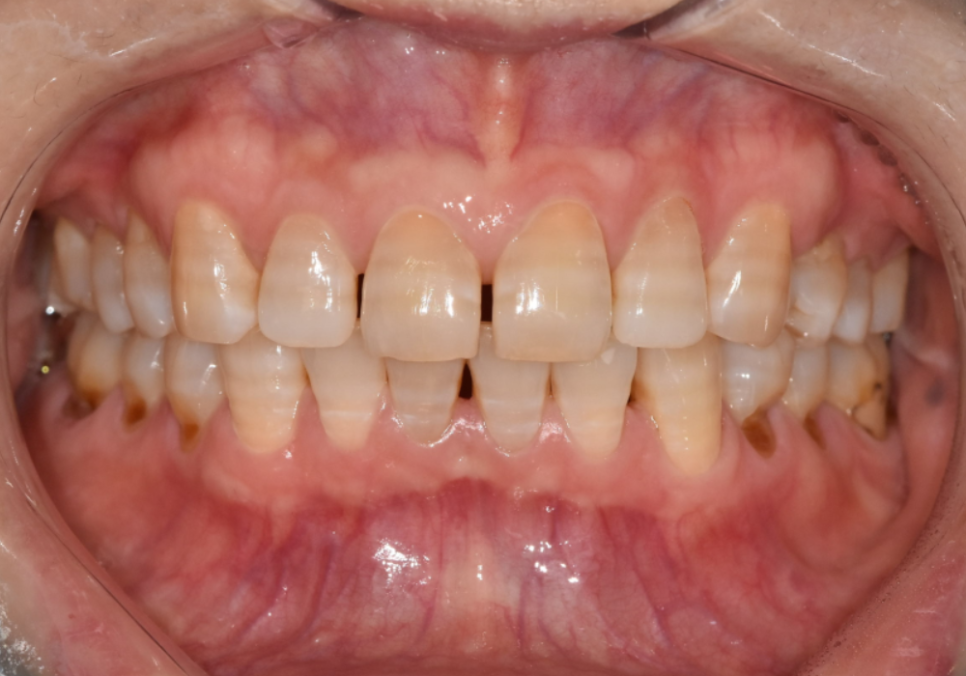

라미네이트로 개선한 실제 사례

얼마 전에 내원하신 한 환자분이 특히 기억에 남습니다.

앞니가 벌어져 있고,

갈색 가로줄이 선명하게 보여서 웃을 때마다

입을 가리게 된다고 하셨습니다.

250220

자세히 보니 전형적인 항생제 변색이었습니다.

대신, 라미네이트로 치아 벌어짐과 변색을

동시에 해결하는 것이 가장 효과적이라고 설명드렸습니다.

환자분도 오랜 고민 끝에 결정하셨고,

웃을 때 가장 잘보이는

앞니 4개를 라미네이트로 진행했습니다.

250228

치아 벌어짐을 자연스럽게 메우면서도

치아가 너무 커 보이지 않도록

크기와 비율을 꼼꼼하게 맞춰 드렸습니다.

색상은 환자분이 원하시는 밝기 범위 안에서,

자연스럽고 건강해 보이도록 제작했습니다.

완성 후에는 갈색 가로줄도 보이지 않게 되었고,

치아 색도 밝고 균일하게 정돈됐습니다.

250307

치아 벌어짐도 자연스럽게 메워져서

웃을 때 자신감이 생겼다고 하셨습니다.

앞니 변색, 치아미백효과 없는 이유 250220(전) 250307(후)